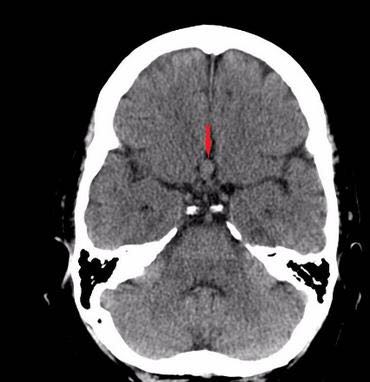

51岁女性,有偏头痛,多方治疗无效